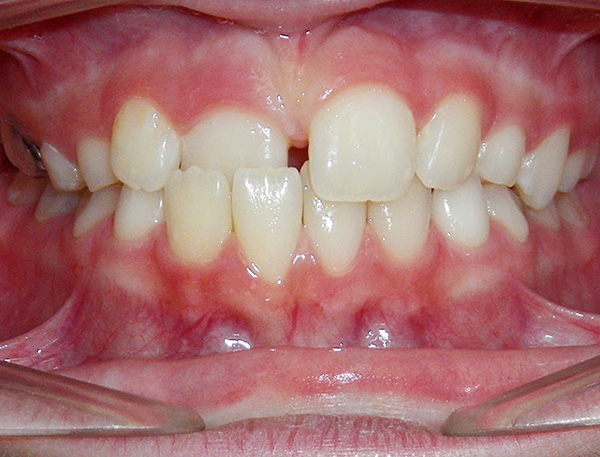

A foto abaixo mostra exemplos de mordida cruzada em uma criança e um adulto:

Mordida cruzada na região anterior - é diagnosticada quando um ou vários dentes estão em uma posição anormal, na maioria das vezes inclinados para o lado da língua, criando assim uma sobreposição nas costas. Por exemplo, um ou dois incisivos podem se cruzar.

A fotografia abaixo mostra um exemplo da mordida cruzada anterior:

Como regra, uma mordida cruzada na parte anterior é combinada com uma mordida mesial anormal na parte lateral da dentição, ou com o deslocamento usual da mandíbula para a frente e a formação de uma mordida cruzada falsa. No segundo caso, é importante entender o motivo pelo qual é mais conveniente para o paciente empurrar a mandíbula para frente.